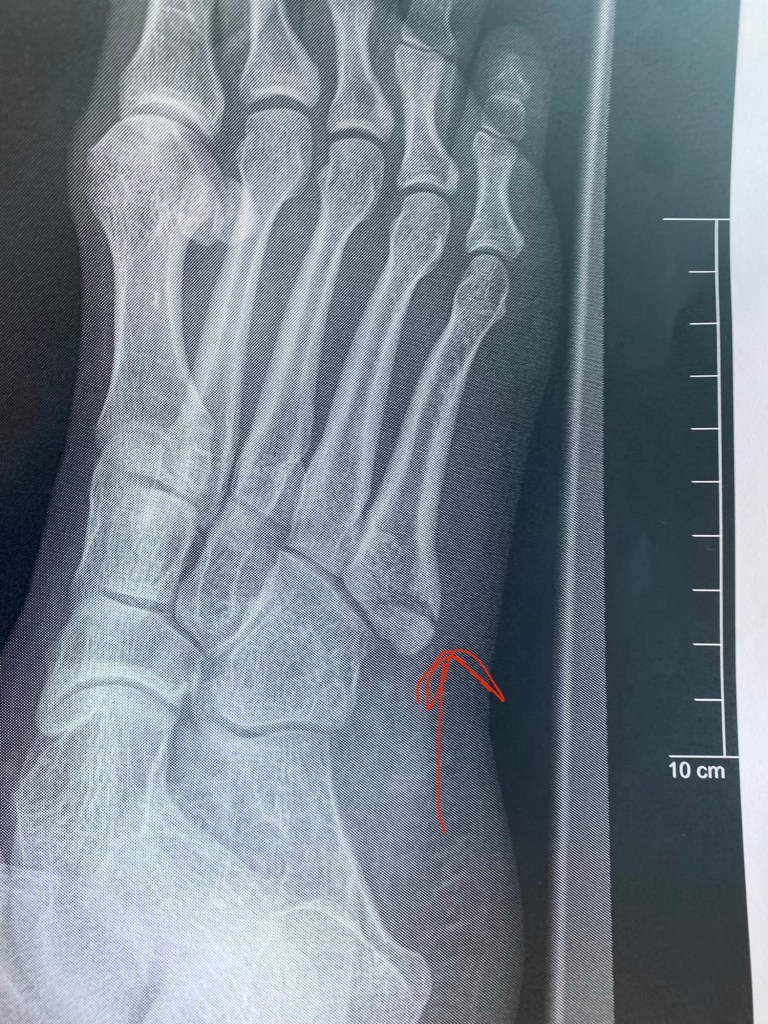

After getting back from Budapest, things hit a bit of a snag. First, I got really sick, probably from my incessant traveling. It started as just a bad cold and devolved into a fever and eventually bronchitis. I used to have really bad asthma as a kid, so when I started wheezing, I finally took my butt to urgent care and got some meds to help open my airways. After a week of pretty much bed rest, I finally started feeling better and decided I needed to go out and get some groceries. This is where the true tragedy begins, LOL. I live on the top floor of my apartment building (Penthouse style, what what!) and made it all the way downstairs to the last step, when suddenly, disaster struck. I sorta missed the step and my foot went wonky and I heard a snap. I collapsed to the ground in pain. Me being the delusional queen that I am, I was like “It’s okay, I probably just sprained it, we’re good.” I hobbled to my car and that was when I realized I truly was delusional. My foot was throbbing and it hurt so bad that I got a little dizzy and clammy. It took me a minute to come to terms with the fact that I probably had broken something. I called my AMAZING friend Jessie who took me to the ER, and after a cool 6 hour visit and a couple of X-rays, it was confirmed that I broke my 5th Base Metatarsal in my right foot. I was put in a hard cast and given crutches with instructions to return in a week for further X-rays. The doctor was unsure whether I would need suregery based on how my bone broke, but he wanted to see how my foot was looking when the swelling went down a bit before making a decision. Thankfully, the follow up X-rays looked good, and despite my entire foot being green and purple from bruising, no surgery was needed. This was a HUGE win because I was emotionally not handling the idea of surgery very well. My hard cast was taken off and I was put in a walking boot for 6 weeks. I had to use crutches still for another 2 weeks in combination with the boot before I could comfortably put weight on my foot, but I am stoked to say that tomorrow is officially 6 weeks post-break and I seem to have healed really well. I have no more bruising and very minimal pain, mostly when I have done a lot of walking and need to rest it. I’m starting to walk without the boot for short durations at a time and I’m feeling pretty good. My tendons and ankle are super tight from lack of use so I feel like I’m walking pretty funny, but I know that will get better with time. HUGE shout out to my guy Jessie though who drove me to all my appointments and took me to get groceries and drove my butt to work for like 2 weeks straight. Really could not have survived this without his friendship and I cannot thank him enough.